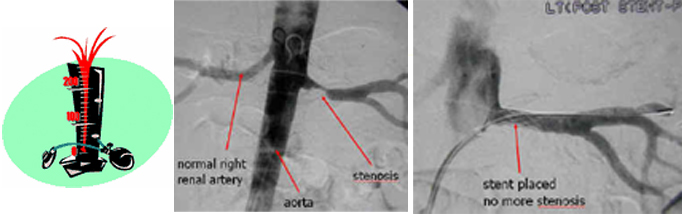

Renovascular Hypertension – is suspected in patients with high blood pressure that is difficult to control or that requires more than 3 drugs and may be associated with worsening of kidney function or kidney failure.